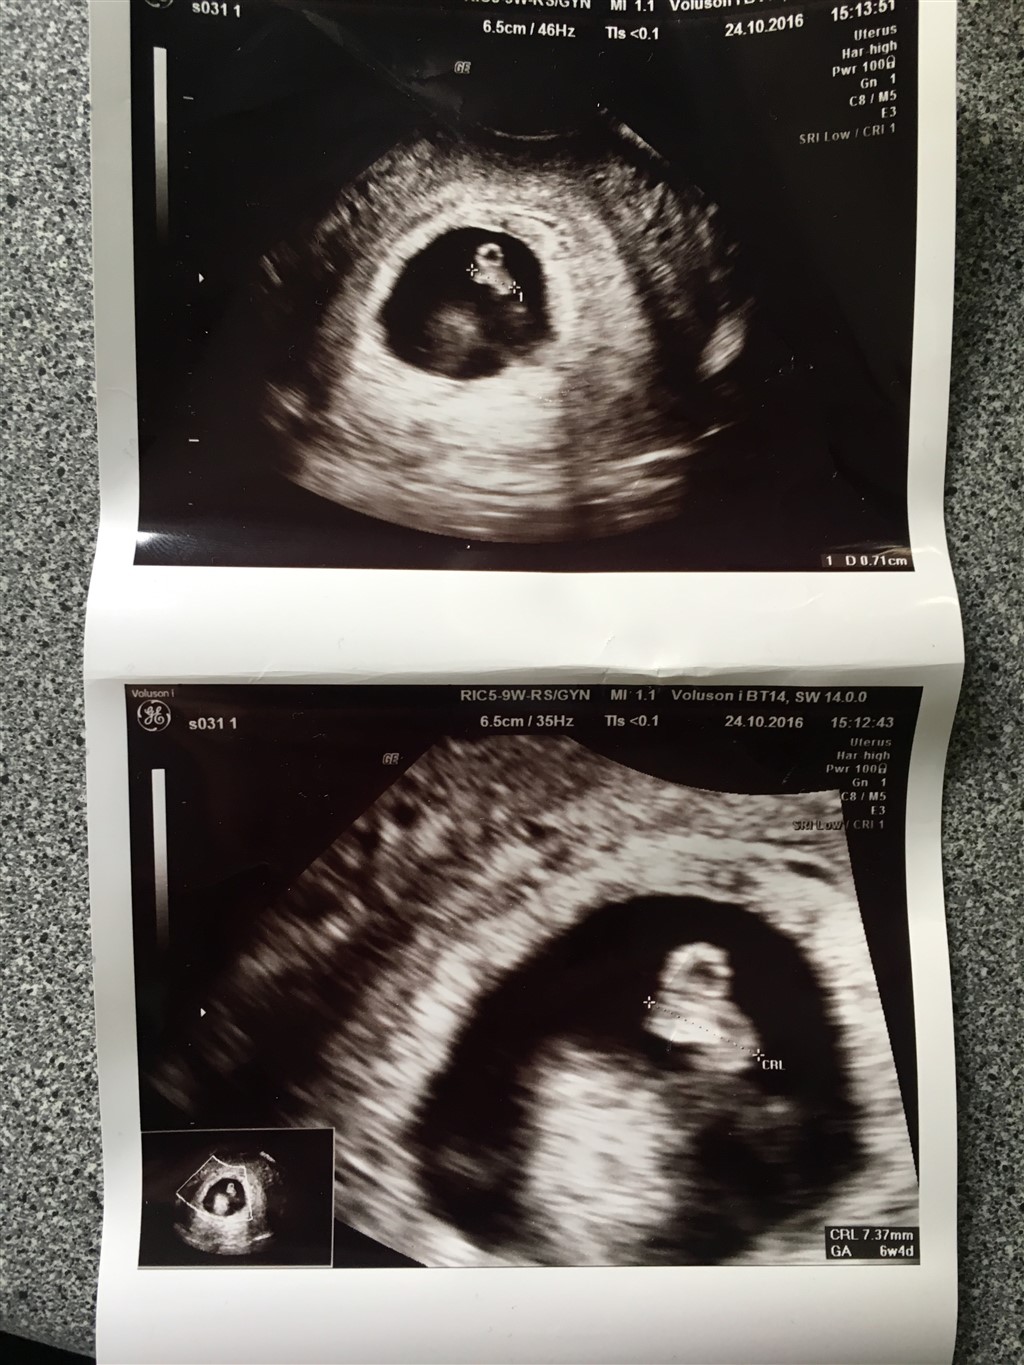

Jeg var til tidlig scanning igår (6+4), og alt så fint ud. Jeg fik dette billede med hjem, og nu da jeg er kommet hjem kan jeg se at det er som om at der er en hvid "klump" ved siden af fosteret  Det er min tredje graviditet, og de andre gange har der bare været sort omkring fosteret. Nogle der ved hvad det er?  Det er selvfølgelig bare ren nysgerrighed, går ud fra at lægen havde sagt hvis det var noget alvorligt

Jo, lægen sagde at den lille runde der ligger helt tæt op af fosteret er blommesækken  Det er mere den anden store hvide skygge der er i livmoderen jeg undrer mig over

Er ikke lige i nærheden af en computer, men jeg kan prøve at forklare det lidt bedre  Altså der hvor fosteret ligger kan man se, at han har målt det der skal være fosteret. Helt tæt op af fosteret ligger der en lille rund boble som han forklarede var blommesækken. Helt nede i bunden af livmoderen er der så en stor, rund, hvid skygge, som jeg ikke synes ligner noget fra mine gamle scanningsbilleder fra mine tidligere graviditeter  Det er den hvide "skygge" jeg refererer til

Jeg vil bare lige pointere at blæren IKKE er lys/hvid på ultralyd. Blæren vil altid fremstå helt sort Desuden ligger det hvide jo inde i selve livmoderen - anatomisk ville det være lidt mærkeligt hvis blæren lå dér

Jeg har ingen forklaring på hvad det er på TS' billede, men blære er det i hvert fald ikke